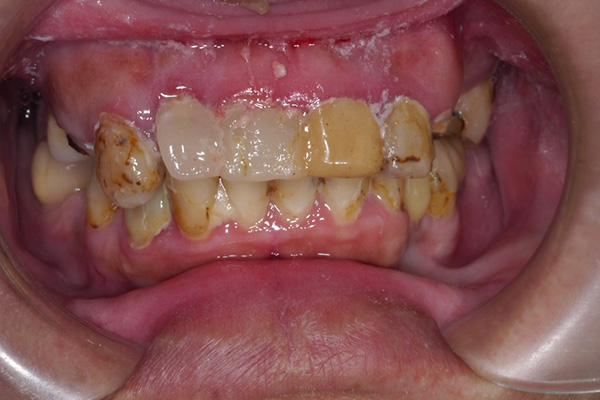

術前:車禍導致嚴重牙齒缺損,臨時假牙不堪使用

![]() |